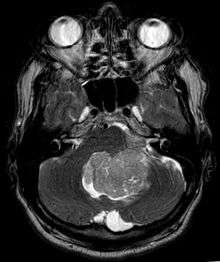

Ependymoma is a tumor that arises from the ependyma, a tissue of the central nervous system. Usually, in pediatric cases the location is intracranial, while in adults it is spinal. The common location of intracranial ependymoma is the fourth ventricle. Rarely, ependymoma can occur in the pelvic cavity.

Ependymomas make up about 5% of adult intracranial gliomas and up to 10% of childhood tumors of the central nervous system (CNS). Their occurrence seems to peak at age 5 years and then again at age 35. They develop from cells that line both the hollow cavities of the brain and the canal containing the spinal cord, but they usually arise from the floor of the fourth ventricle, situated in the lower back portion of the brain, where they may produce headache, nausea and vomiting by obstructing the flow of cerebrospinal fluid. This obstruction may also cause hydrocephalus. They may also arise in the spinal cord, conus medularis and supratentorial locations.[4] Other symptoms can include (but are not limited to): loss of appetite, difficulty sleeping, temporary inability to distinguish colors, uncontrollable twitching, seeing vertical or horizontal lines when in bright light, and temporary memory loss. It should be remembered that these symptoms also are prevalent in many other illnesses not associated with ependymoma.

About 10% of ependymomas are benign myxopapillary ependymoma (MPE). MPE is a localized and slowly growing, low-grade tumor. Although some ependymomas are of a more anaplastic and malignant type, most of them are not anaplastic. Well-differentiated ependymomas are usually treated with surgery. For other ependymomas, total surgical removal is the preferred treatment in addition to radiation therapy. The malignant (anaplastic) varieties of this tumor, malignant ependymoma and the ependymoblastoma, are treated similarly to medulloblastoma but the prognosis is much less favorable. Malignant ependymomas may be treated with a combination of radiation therapy and chemotherapy. Ependymoblastomas, which occur in infants and children younger than 5 years of age, may spread through the cerebrospinal fluid and usually require radiation therapy. The subependymoma, a variant of the ependymoma, is apt to arise in the fourth ventricle but may occur in the septum pellucidum and the cervical spinal cord. It usually affects people over 40 years of age and more often affects men than women.